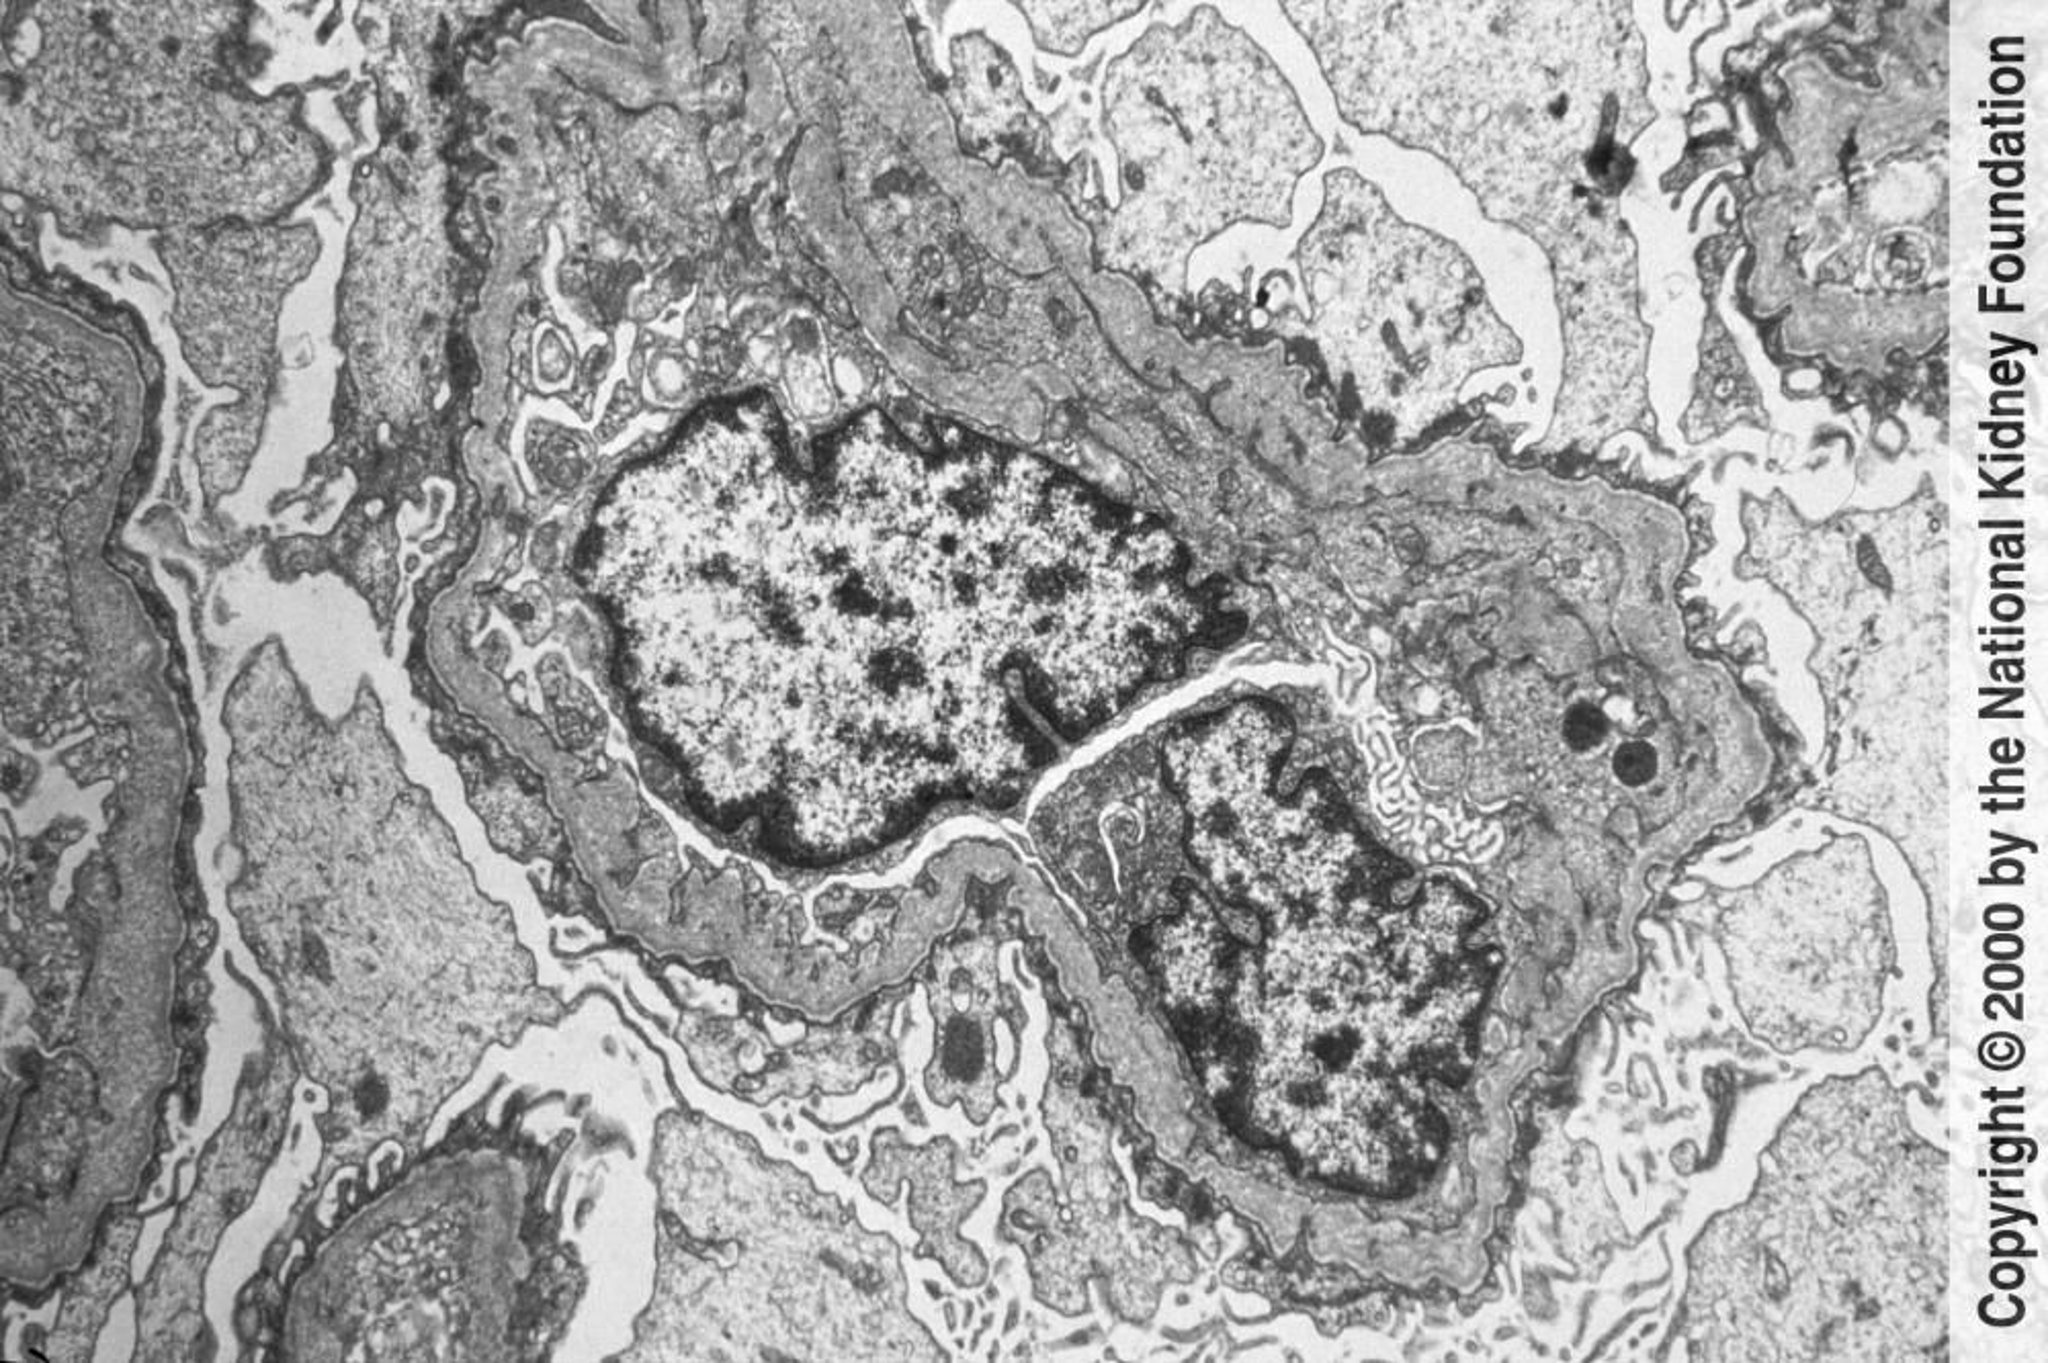

Glomerular basement membranes show irregular thinning and thickening with a lamellated basket-weave appearance under transmission electron microscopy. The changes are caused by injury and remodeling (×6000).

Image provided by Agnes Fogo, MD, and the American Journal of Kidney Diseases' Atlas of Renal Pathology (see www.ajkd.org).